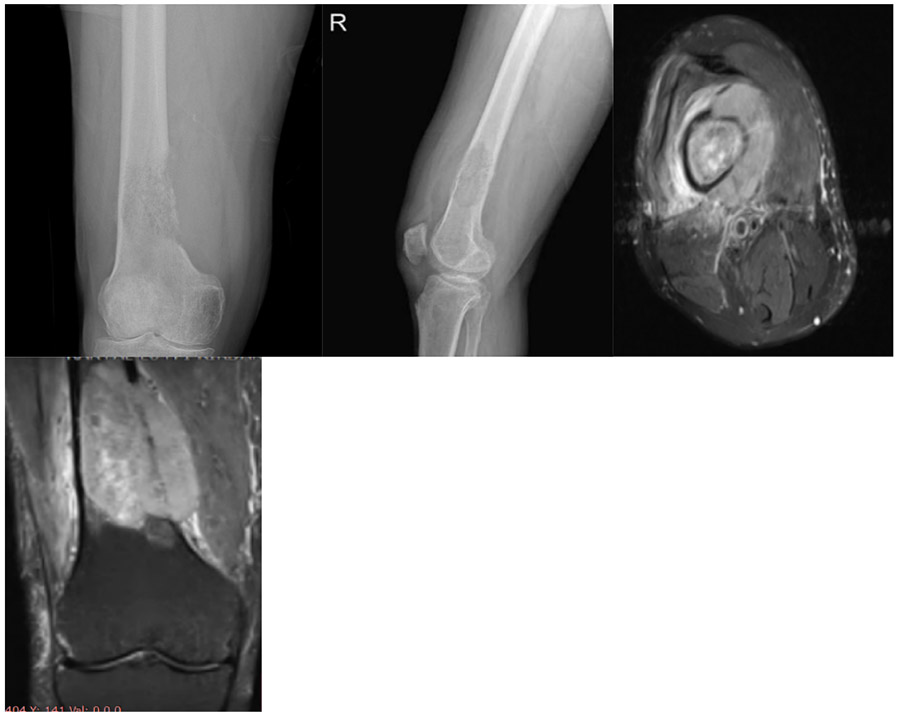

CASE 43: Lung cancer increases the risk of fracture due to metastasis of the lower end of the right thigh (femur).

Before the surgery: X-ray shows erosion and destruction in the medial distal end of the right femur, and MRI shows an accompanying tumor mass and surrounding edema.